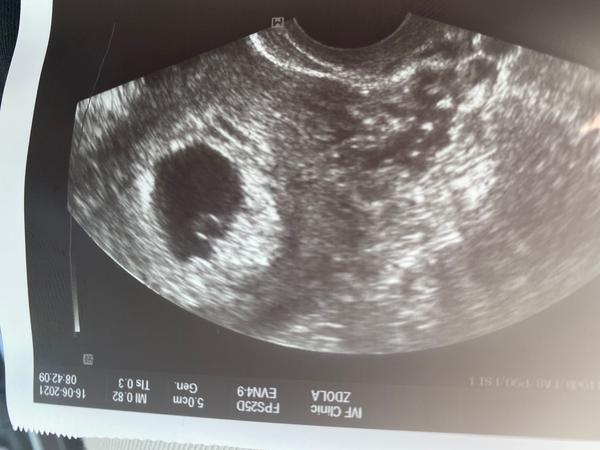

@veeev holkyyyyy je tam jedno a už začíná srdeční akce💗💗💗💗